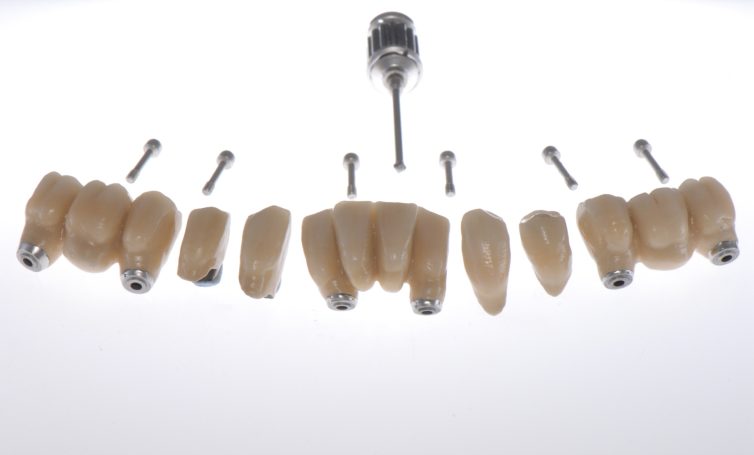

Metallfreie Frontzahnkronen mit individueller keramischer Verblendung.

Frontzahnkrone auf Implantat zum Lückenschluss des seitlichen Frontzahnes.